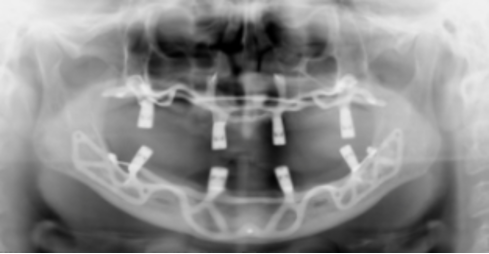

🔹 Intervento chirurgico con griglia iuxtaperiostea in titanio

🔹 4 Impianti in titanio biocompatibile

🔹 Visite, TAC, radiografie ed esami inclusi

✅ TAC e panoramiche